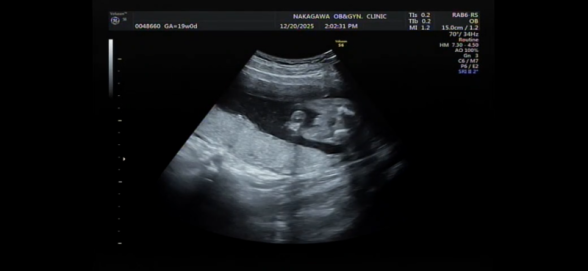

19週になりましたが、まだ性別がわかりません。 正月に家族とも話したいなーと思っているのですが 次の検診が年明けなので もし分かるのであれば教えて欲しいです!

へその緒が近くにあるのでわかりづらく、、

確定はできないのはわかっていますが多分どっちかでも知りたいです、、!

お腹の赤ちゃんの性別についてですね。

添付をしてくださった画像を拝見いたしました。

男の子のシンボルとなりそうなものがありそうに見えあたり、なさそうにも見えたりと、どちらかということもお返事がしにくい状況でした。

せっかくご相談いただいていたのに、大変申し訳ありません。

次回の健診の時に、ご確認いただけたらと思います。